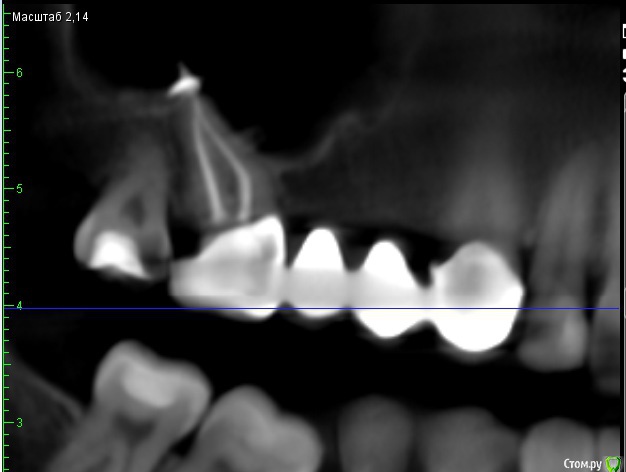

red_butler Опубликовано 20 июня, 2015 Поделиться Опубликовано 20 июня, 2015 Делайте Кт, для начала нужно исключить четвертый корневой канал. Скорее всего понадобится консультация ЛОРа. Узнайте у своего врача, чем пломбировали каналы. Ссылка на комментарий

Natcar Опубликовано 22 июня, 2015 Автор Поделиться Опубликовано 22 июня, 2015 Готово КТ , две ссылки на сайт файлообменника и облако майлруhttp://fayloobmennik.com/iir66p9dhmvl/0011.zip.htmlhttps://cloud.mail.ru/public/3UBG/8CR2mFiZW В клинике где делала снимок возникли вопросы по нижнему зубу -вроде как плохо запломбированный канал. У меня , кстати есть шишка при пульпации щеки на месте этого зуба. Беспокоит и может увеличиваться при простудах. Также слева сверху у семерки увидели незапломбированный канал. Хотя я в мае сходила на лечение в ходе которого мне установили на него коронку. Проблемы с зубом который меня беспокоит сейчас-ничего, кроме того, что много материала выведено за верхушку. В общем, растройстроена. Ссылка на комментарий